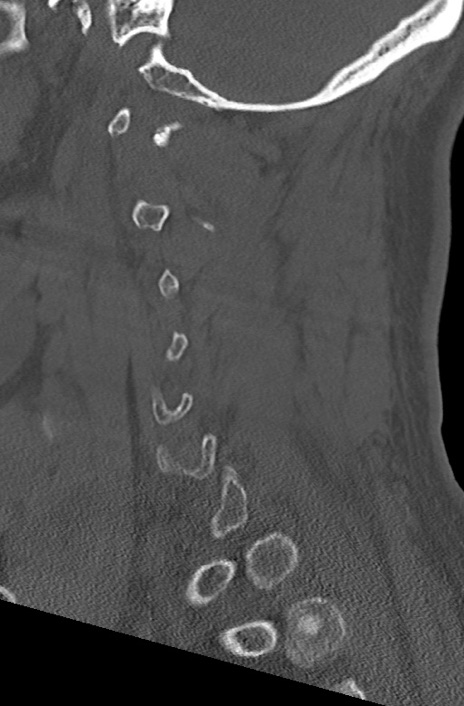

頚椎CT

冠状断像